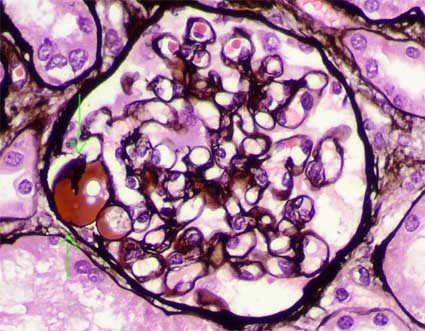

The characteristic histologic feature is sclerosis of segments of the glomerular tuft in some glomeruli (“segmental and focal”), with mesangial expansion and capillary lumen loss in these segments. The injury can be more notorious in the vascular pole or in the periphery of the tuft. When advancing the process the sclerosis becomes global and is indistinguishable of the secondary sclerosis to other diseases. The sclerosing segments are positive with PAS and silver-methenamine stains (type IV collagen). From the Fifties it is said that juxtamedullary glomeruli are more compromised by the segmental lesions. There are, in many cases, podocyte hypertrophy and hyperplasia, mainly on the surface of the sclerosed tuft segment (“cap lesion” or “cellular lesion”). Podocytes frequently appear with protein droplets and lipid resorption. The glomeruli without sclerosing lesions can appear normal or with increase of the mesangial cellularity and, sometimes, hypertrophic (glomerulomegaly).

Figure 1. Glomerular tuft segmental sclerosis in the superior half; segments in the inferior half display mesangium and capillary walls and lumens with conserved architecture. (Masson’s trichrome, X400).

Figure 2. With methenamine-silver stain the segments with loss of the capillary structure and sclerosis are better seen. The podocytes that cover these segments present hypertrophy and hyperplasia. (Methenamine-silver, X400).